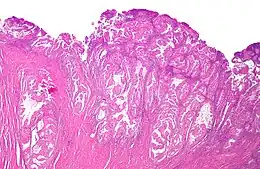

Coupe histologique d'un adénocarcinome endométrioïde, la forme la plus fréquente de cancer de l'endomètre. Coloration à l'hématoxyline et à l'éosine.

Le cancer de l'endomètre est un carcinome, principalement un adénocarcinome, de différenciation glandulaire.

Les carcinomes de l'endomètre sont de plusieurs types histologiques : l'adénocarcinome endométrioïde est le plus fréquent (75 à 80 % des cas[7]), suivi du carcinome mixte (10 %), de l'adénocarcinome séreux (moins de 10 %, de mauvais pronostic et qui se traite comme un cancer de l'ovaire). Seule la forme endomètioïde est sensible aux hormones. L'adénocarcinome non endomètrioïde se voit plus fréquemment chez l'afro-américaine, avec un plus mauvais pronostic[7].